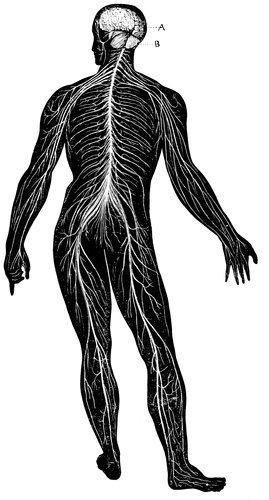

THE NERVOUS SYSTEM.

The muscles which move the bones are themselves moved by the nerves. The nerves are soft and pulpy in youth, but harden as you advance in years. They are composed of a gray substance, called the nerve-cell, and a white substance, known as the nerve-fibre.

The brain is the mass of nervous tissue within the skull. It is so tender and easily harmed that nature has walled it 92about by a hard, bony structure to protect it from injury.

The gray substance of the nerves is where nervous impulses begin, which are conducted along the white substance. The gray matter may be compared to a telegraph office where the message is started, while the white matter is the wire along which the message travels.

The spinal cord, or marrow, is a mass of soft, nervous tissue, which fills the 93hollow running the length of the spine or backbone.

From the base of the brain twelve pairs of nerves are given off to the face and head. One pair passes to the eye, and gives sight; one passes to the nose, and 94gives smell; one, to the mouth, tongue, and palate, and gives taste; one, to the ears, and gives hearing; and others to the face, neck, and head, and give the expressions of joy, sorrow, pain, anger, and doubt.

From the spinal cord thirty-one pairs of nerves pass to the various parts and organs of the body.

There could be no motion or feeling without the nerves, although they are not the true centres of either. If you obey the rules of health, as already laid down, you will be in the happy condition of those of whom it is said they do not feel that they have any nerves at all.